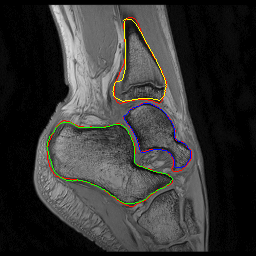

Fig. 2: Visual comparison of UNet regularization methods: baseline UNet [2], adversarial regularization [6], shape priors based regularization [7] and the proposed shape priors based adversarial regularization on ankle dataset. Ground truth delineations are in red (). Predicted bones, calcaneus, talus and tibia respectively appear in green (), blue () and yellow ().

Experiments were conducted on two pediatric datasets previously acquired using a 3T Philips scanner [4]. The two MR images datasets were independently acquired on two musculoskeletal joints (ankle, shoulder) from a cohort of 17 and 15 pediatric patients. An expert (12 years of experience) annotated images to get ground truth contours of calcaneus, talus and tibia for ankle, as well as scapula and humerus for shoulder. All axial slices were downsampled to 256×\times256 pixels.

We compared the proposed shape priors based adversarial regularization method (SPAR in Fig.1) with baseline UNet (Base. UNet) [2], adversarial regularization (Adv. Reg.) [6] and shape priors based regularization (Sh. Reg.) [7]. For all methods, the backbone UNet architecture and all training hyper-parameters remained the same. All networks were trained from scratch with randomly initialized weights.

From the quantitative results (Tab.1), our method achieved competitive results compared to state-of-the-art on both datasets. On ankle dataset, our approach ranked best in Dice (92.7%percent\%), RAVD (8.0%percent\%), ASSD (0.8mm) and MSSD (8.1mm) metrics. For shoulder dataset, our method outperformed other approaches in RAVD (13.6%percent\%) while remaining second best in Dice (0.3%percent\% lower than the best) and ASSD (0.3mm higher than the best). We suspected that the high variability observed in shoulder results was due to the poor quality of two outlier examinations. The visual comparisons (Fig.2) provided the evidence of gradual improvements in segmentation quality of the regularized methods over baseline UNet. We wanted to report statistical significance tests to compare the performance of the employed methods but the required sample size determined using a power analysis (with typical statistical power β=0.8𝛽0.8\beta=0.8) was larger than our available datasets.